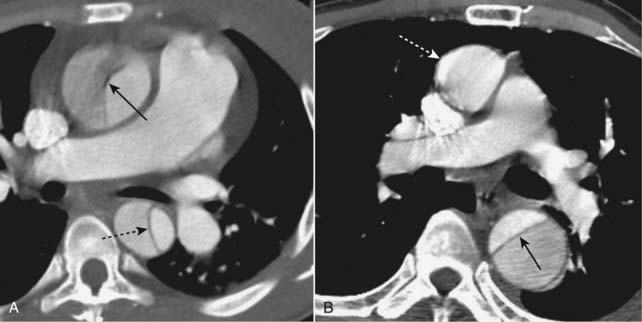

image Pleural effusion

As a result of either increased production or decreased absorption of pleural fluid, fluid in excess of the normal 2-5 mL can collect in the pleural space, typically at a pulmonary capillary wedge pressure of about 20 mm Hg.

Pleural effusions accompanying CHF are usually bilateral but can be asymmetric (Fig. 9-15).

When unilateral, they are almost always right-sided.

About 15% the time, they can be unilateral and on the left, but if you see a unilateral left pleural effusion, you should think of causes other than CHF, like metastases, tuberculosis, or pulmonary thromboembolic disease.

image

Figure 9-15 Pleural effusions in congestive heart failure.

Bilateral pleural effusions (dotted and solid black arrows) are present in this patient with CHF. Effusions in CHF are most often bilateral but may be asymmetrical, the right side invariably being slightly larger. While a unilateral, left pleural effusion may occur with CHF, a large left effusion should draw suspicion to another possible cause, such as metastatic disease.